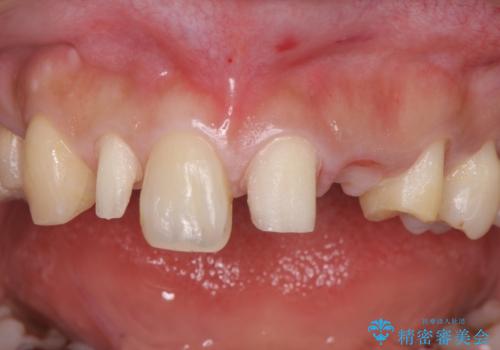

前歯の審美的なブリッジ (歯列矯正後)

- 歯列矯正後に前歯にブリッジを入れた方の経過です。

- 66万円 内訳:ジルコニアクラウンブリッジ(スペシャル) 15.4万円×4本、仮歯 1.1万円×4本費用は治療当時の料金となります

矯正治療で歯の位置を整えてからブリッジを入れると歯の幅を自由に設定できるため、左右対称にできます。結果矯正なしでいきなりセラミックにする場合と異なり、無理に角度を変えたりする必要がなく、神経をなるべく温存したまま審美的なセラミック治療が行えます。